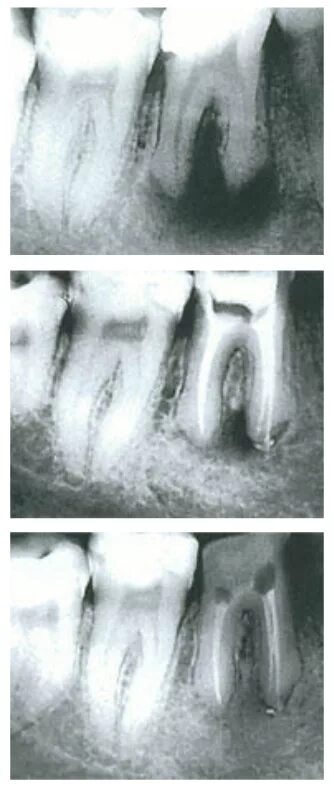

Киста зуба что это